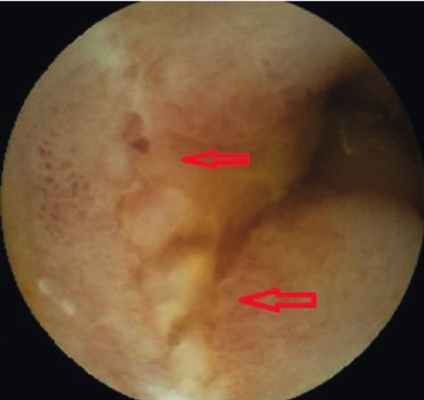

Пациентка В . , 19 лет, с подтвержденным диагнозом «болезнь Крона (язвенно-геморрагический энтерит)» с 2012 г. неоднократно находилась на обследовании и лечении в отделении воспалительных заболеваний кишечника Московского клинического научно-практического центра. Длительное время получала месалазин, азатиоприн, инфликсимаб; неэффективность проведенного лечения послужила поводом для назначения биологической терапии (адалимумаб). Однако стойкой ремиссии добиться не удавалось. При очередном обследовании в марте 2015 г. пациентке была выполнена колоноскопия, во время которой выявили незначительные воспалительные изменения ободочной кишки и терминального отдела подвздошной кишки: афтозный колит, афтозный терминальный илеит. Данные, полученные при традиционной эндоскопии, не соответствовали клиническому состоянию больной. Для оценки распространенности и степени поражения кишечника ей была назначена КЭ. В результате видеокапсульного исследования определено поражение глубоких отделов тонкой кишки на значительном протяжении в виде множественных язв и отека складок, а также обнаружено сужение просвета тонкой кишки ( рис. 1-4 ).

Рис. 3. Язвы слизистой оболочки тонкой кишки, формирующийся рубец. Фото авторов